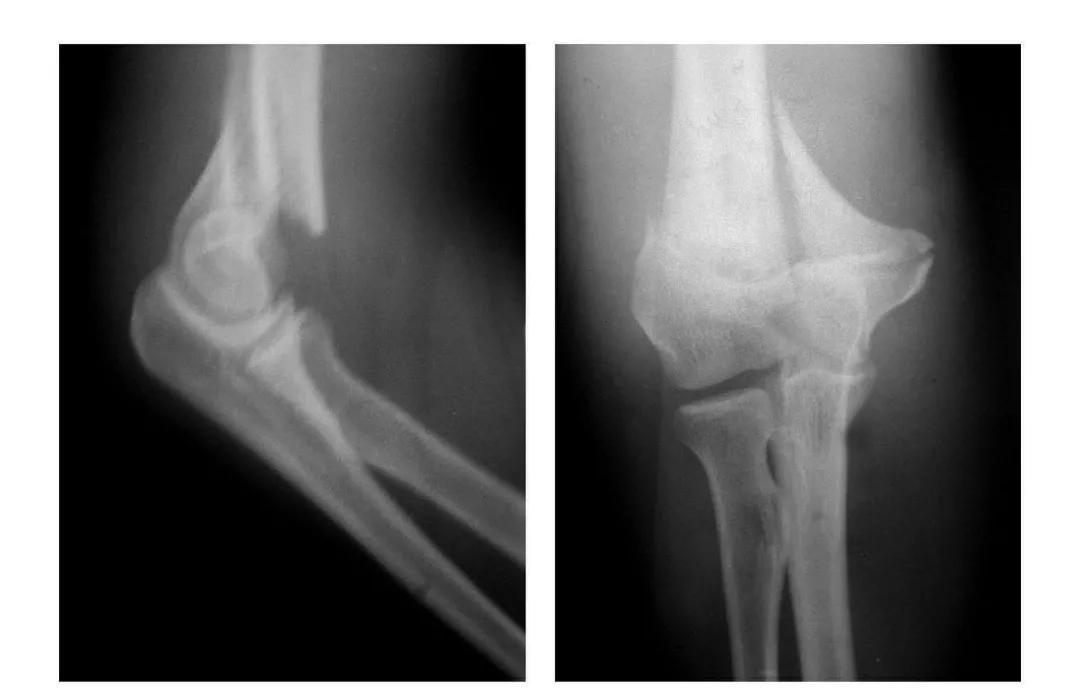

肘关节爆裂性脱位

本病亦称三关节脱位。

例1:肘关节内外型爆裂性脱位(即肘关节后脱位并上尺桡关节向内外侧分离)。

例2:肘关节前后型爆裂性脱位(即桡骨脱向肘前上,尺骨脱向肘后上)。

例3:其主要病变同例1并同侧桡骨远端骨骺滑脱。

肘关节习惯性脱位

例1:肱骨滑车及尺骨冠状突发育不全,致肘关节不稳而呈习惯性脱位。

例2:尺桡骨近端发育不全,致肘关节不稳而呈习惯性脱位。